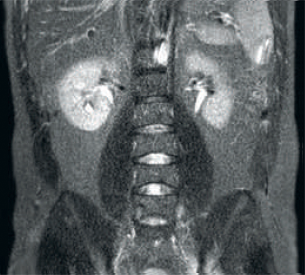

Risultato: miglioramento del rapporto segnale-rumore e della risoluzione delle immagini

Risultato: immagini disturbate con parametri di scansione identici

Maggiore coerenza e migliore qualità dell'immagine La tecnologia di ricezione RF dStream digitalizza il segnale RM direttamente nella bobina RF, con un aumento fino al 40% del rapporto segnale-rumore* in tutto il volume dell'immagine. Semplificazione del flusso di lavoro e aumento della produttività La bobina posteriore integrata nel piano portapaziente elimina la manipolazione delle bobine nel 60% degli esami. Le bobine anteriori leggere e adattabili e la possibilità di connettere la bobina con un singolo cavo e una sola mano ne rendono più facile l'uso.